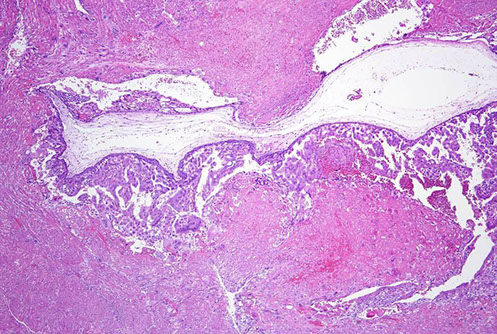

Chorangioma

most common type of placental neoplasm, with an

overall incidence of <1%. Typically, they are asymptomatic and are discovered incidentally at birth through gross examination of the placenta revealing a wellcircumscribed, spongy, red-brown nodule within the placental parenchyma, commonly at the periphery of the disc or directly below the cord insertion. Occasionally, multiple chorangiomas can be present. Most are discovered in mature placentas at 32-37 weeks’ gestation in mothers over the age of 30. Increasing maternal age has been correlated with increased incidence of chorangiomas. They are thought to develop as a reactive proliferation to hypoxia resulting in increased vascular endothelial growth factor production and angiogenesis. While most are incidentally found and have no clinical consequences, large chorangiomas (>4 cm)

may be associated with intrauterine growth restriction (IUGR), arterio-venous shunting, and fetal cardiac failure. Chorangiomas express GLUT1, similarly to

infantile hemangiomas, and may occur concurrently. While debated in the literature, some studies have shown a possible association between infantile hemangiomas and chorangiomas and even speculate that infantile hemangiomas may result from endothelial cell shedding from chorangiomas or hormonal influence during development.

Micro: well-circumscribed vascular proliferation composed of numerous capillaries. Examination of the nodule under high power reveals that the capillaries are surrounded by pericytes with no cytologic atypia. Mitotic figures are not readily identifiable. Surrounding the nodule, there are benignappearing cytotrophoblasts and syncytiotrophoblasts with appropriate syncytial knotting for gestational age. The few villi present surrounding the nodule are small,

mature, and appropriately developed for a third trimester placenta with a normal amount of vessels present